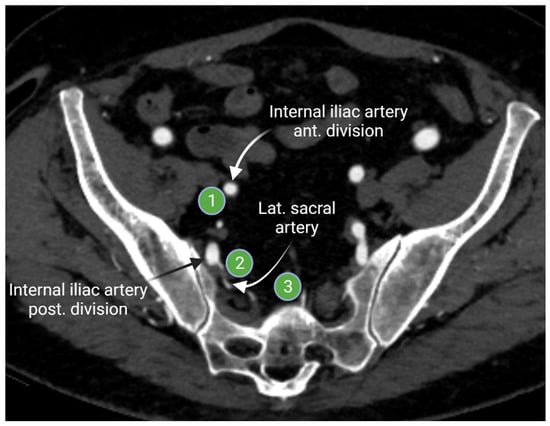

2.1.2. Iliac Lymph Nodes Anatomy

- McMahon, C.J.; Rofsky, N.M.; Pedrosa, I. Lymphatic Metastases from Pelvic Tumors: Anatomic Classification, Characterization, and Staging. Radiology 2010, 254, 31–46. [Google Scholar] [CrossRef]

- Park, J.M.; Charnsangavej, C.; Yoshimitsu, K.; Herron, D.H.; Robinson, T.J.; Wallace, S. Pathways of nodal metastasis from pelvic tumors: CT demonstration. Radiographics 1994, 14, 1309–1321. [Google Scholar] [CrossRef]

- Fukuda, H.; Nakagawa, T.; Shibuya, H. Metastases to pelvic lymph nodes from carcinoma in the pelvic cavity: Diagnosis using thin-section CT. Clin. Radiol. 1999, 54, 237–242. [Google Scholar] [CrossRef]